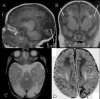

Congenital hyperinsulinism (HI) is an inappropriate insulin secretion by the pancreatic β-cells secondary to various genetic disorders. The incidence is estimated at 1/50, 000 live births, but it may be as high as 1/2, 500 in countries with substantial consanguinity. Recurrent episodes of hyperinsulinemic hypoglycemia may expose to high risk of brain damage. Hypoglycemias are diagnosed because of seizures, a faint, or any other neurological symptom, in the neonatal period or later, usually within the first two years of life. After the neonatal period, the patient can present the typical clinical features of a hypoglycemia: pallor, sweat and tachycardia. HI is a heterogeneous disorder with two main clinically indistinguishable histopathological lesions: diffuse and focal. Atypical lesions are under characterization. Recessive ABCC8 mutations (encoding SUR1, subunit of a potassium channel) and, more rarely, recessive KCNJ11 (encoding Kir6.2, subunit of the same potassium channel) mutations, are responsible for most severe diazoxide-unresponsive HI. Focal HI, also diazoxide-unresponsive, is due to the combination of a paternally-inherited ABCC8 or KCNJ11 mutation and a paternal isodisomy of the 11p15 region, which is specific to the islets cells within the focal lesion. Genetics and 18F-fluoro-L-DOPA positron emission tomography (PET) help to diagnose diffuse or focal forms of HI. Hypoglycemias must be rapidly and intensively treated to prevent severe and irreversible brain damage. This includes a glucose load and/or a glucagon injection, at the time of hypoglycemia, to correct it. Then a treatment to prevent the recurrence of hypoglycemia must be set, which may include frequent and glucose-enriched feeding, diazoxide and octreotide. When medical and dietary therapies are ineffective, or when a focal HI is suspected, surgical treatment is required. Focal HI may be definitively cured when the partial pancreatectomy removes the whole lesion. By contrast, the long-term outcome of diffuse HI after subtotal pancreatectomy is characterized by a high risk of diabetes, but the time of its onset is hardly predictable.